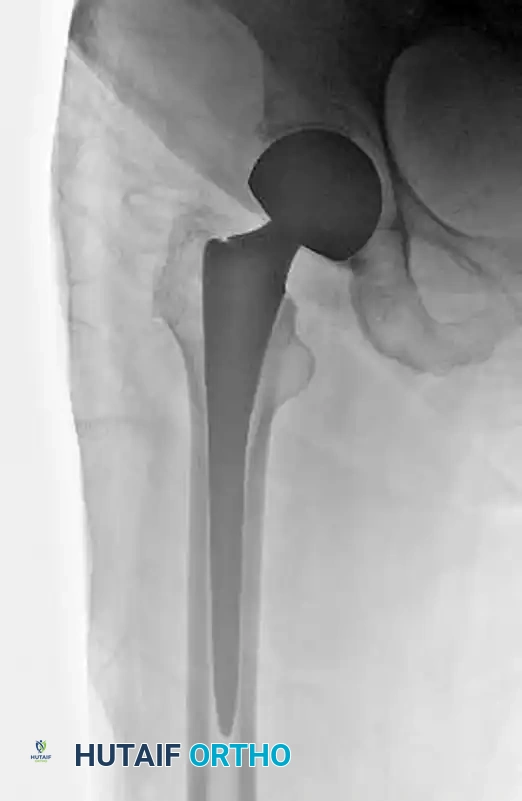

4. Plate Application

- Slide the side plate over the lag screw shaft and advance it onto the lateral aspect of the femur.

- Use a tamp to fully seat the plate barrel over the screw and flush against the lateral cortex.

- Remove the lag screw retaining rod, the insertion wrench, and finally, the guide pin.

5. Cortical Fixation and Compression

- Secure the side plate to the femoral shaft using a bone clamp.

- Drill, measure, tap (if necessary), and place two to four bicortical 4.5-mm cortical screws through the plate into the femoral shaft. If a screw was initially used to pull the plate to the bone, it may need to be exchanged for a shorter one once the plate is fully seated.

- Release the traction on the fracture table.

- If additional impaction is desired, insert a compression screw into the back of the lag screw. Alternatively, manual compression can be applied by gently pushing the leg proximally.

Because the compression hip screw is primarily utilized for stable fracture patterns (A1 and A2.1), the postoperative protocol is generally aggressive.

- Weight-Bearing: Patients are typically allowed to bear weight as tolerated (WBAT) immediately postoperatively. The dynamic sliding nature of the implant relies on physiological loading to impact the fracture site and promote primary stability.

- Physical Therapy: Early mobilization is critical to prevent deep vein thrombosis (DVT), pulmonary embolism, pneumonia, and decubitus ulcers.

- Radiographic Follow-up: Serial radiographs should be obtained at 2 weeks, 6 weeks, and 3 months to monitor for progressive sliding, fracture union, and to ensure there is no evidence of varus collapse or lag screw cut-out.